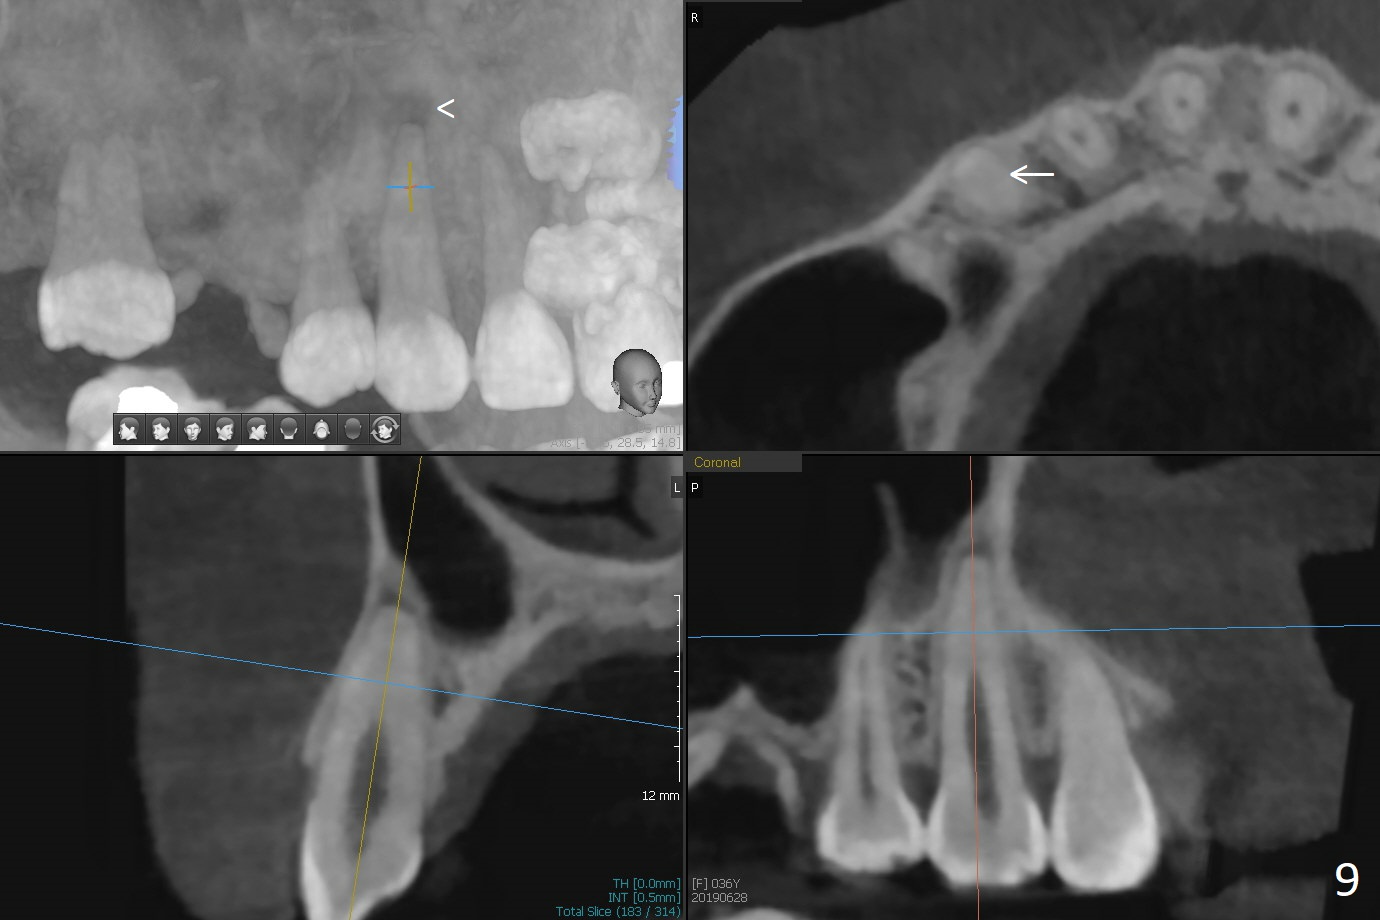

A 36-year-old woman is nervous about dentistry. She will take Valium by herselft before surgery (Fig.1). The tooth #3 has 3 residual roots (Fig.2 (CBCT 3 D occlusal view)). The bone is 2-3 mm thick (Fig.3,4 (sagittal, coronal sections)). A 5x7.3 mm implant will be placed with IS guide (Fig.5 (12 mm offset)). Since IBS implants are able to achieve amazing stability in the thin bone, prepare the shortest 4-5 mm in diameter dummy implants (IS (better surface treatment) and IBS) after sinus lift using UF Guided Sinus Lift Approach Kit (surgery). With intact tooth structure at #14, the bone height is not much (Fig.6), congenital (genetic) in nature. The infection at #31 is more severe (Fig.7). Extraction will be the 2nd in order. Because of limited bone, it is better to do bone graft first. The patient is concerned about the discolored upper right canine, which should be associated with orthodontics 20 years ago (take photos). The apical canal is obliterated (Fig.8,9 arrow) with periapical radiolucency (arrowhead). In fact the bone at #31 is so little that the tooth will be extracted for socket preservation.